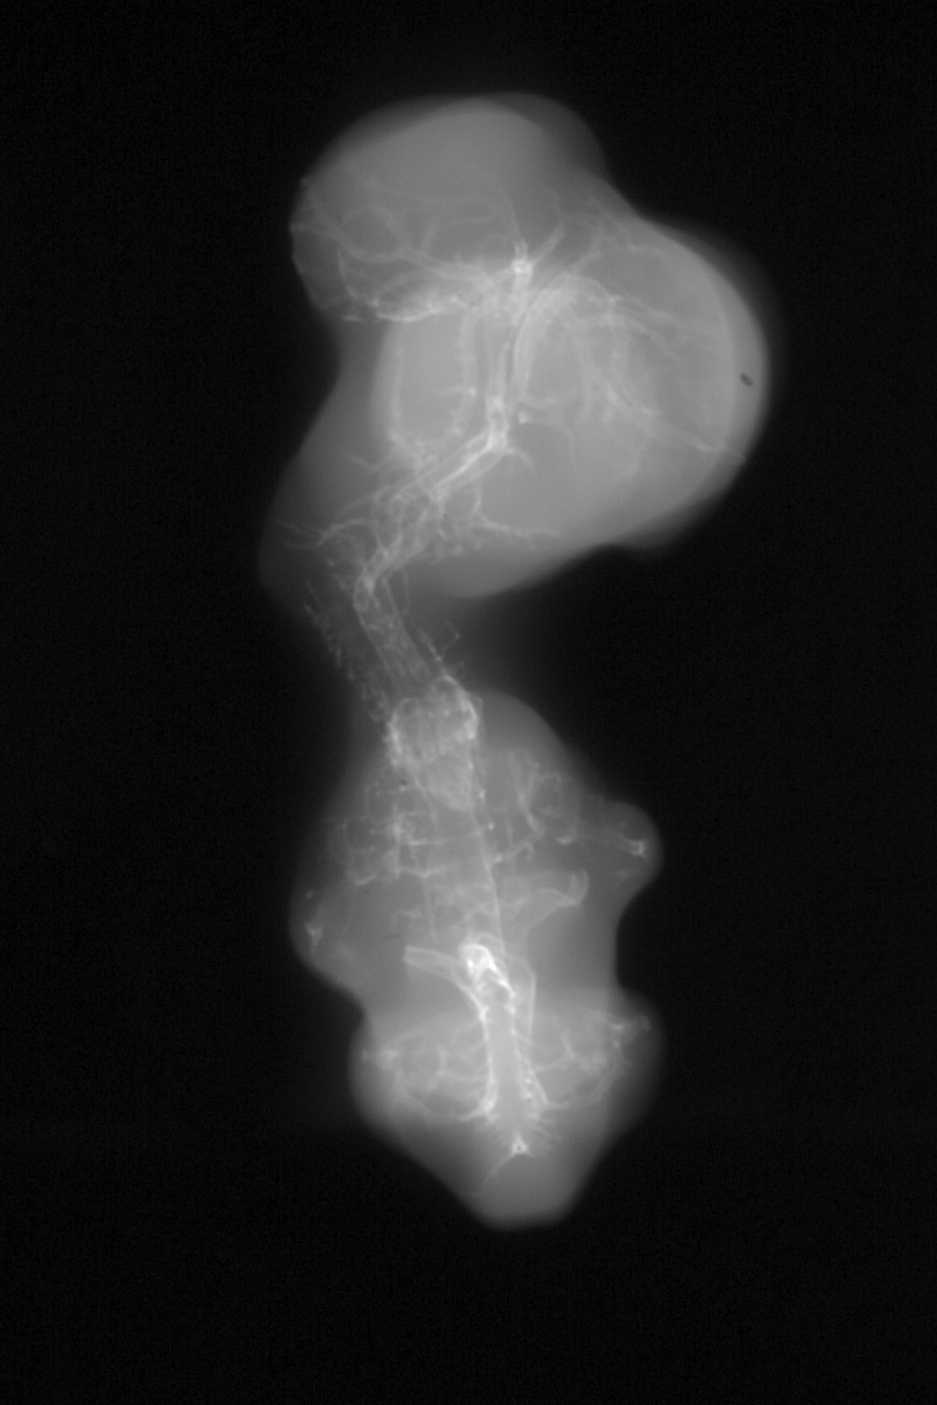

Chick Embryo Microangiography

Hamburger-Hamilton (HH) Stage 28 (approx. 5.5 - 6 days)

Drawing